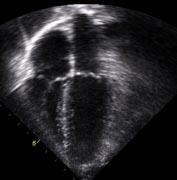

Leading experts in cardiology will present and discuss the latest clinical and research developments in adult and pediatric echocardiography. Among the key presentations are:

• Heart valve surgical candidates can now better predict their risk of dying following surgery: Information from this new study will help patients and families calculate risk of heart valve replacement surgery

• Researchers unveil noninvasive technique for early detection of heart muscle damage in breast cancer patients receiving chemotherapy: Findings help identify cancer patients who may benefit from alternative chemotherapy regimens

• Study finds screening heart and circulation ultrasound can better determine risk of heart disease in obese women: Heart and circulation ultrasound trumps current predictors of heart disease among women with known metabolic risk factors or obesity